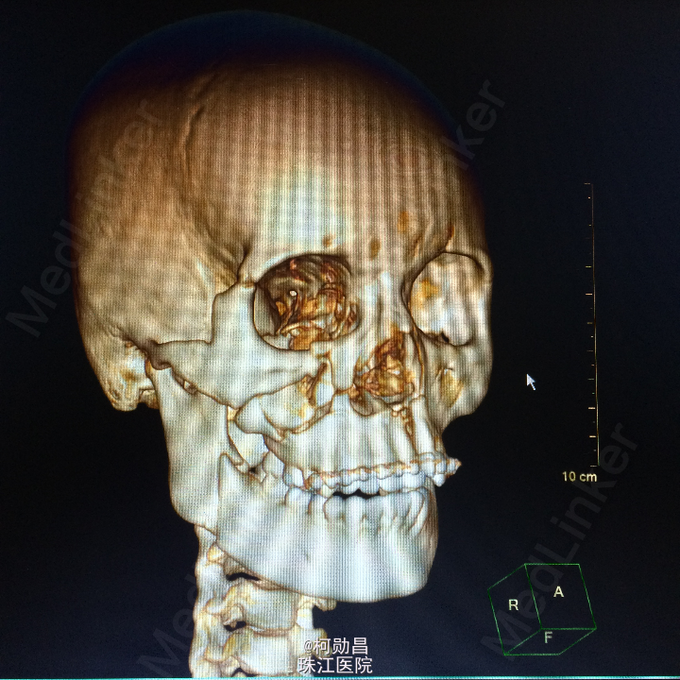

主诉:颅骨损伤后头痛、头晕2天 病史:患者于2天前骑摩托车时与机动车相撞,跌伤头部,至口角、眉弓处多处裂伤出血,左侧外耳道流血,当时患者无意识不清、肢体抽搐等。随即呼叫120送至医院。行头颅CT查示:左顶部硬膜下血肿,蛛网膜下腔出血,予相应治疗后病情稳定 。

查体:脑膜刺激征阳性 辅助检查:复查头颅CT及三维颅骨重建提示:血肿较前吸收,颅骨多发骨折,左额部较为明显

诊断:重型颅脑损伤,脑脊液耳漏、颅骨多发骨折